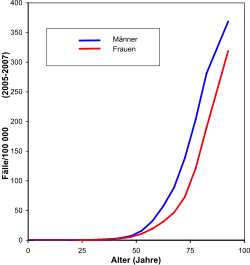

In den Industrieländern hat die Anzahl der Darmkrebsneuerkrankungen seit den 1970er Jahren deutlich zugenommen. Mit einer jährlichen Anzahl von Neuerkrankungen (Inzidenz) in Höhe von weniger als 20 bis 70 pro 100.000 Einwohner[1] ist der Darmkrebs eine der häufigsten bösartigen Erkrankungen in Mitteleuropa. Die weltweite Inzidenz wird auf eine Million Neuerkrankungen pro Jahr geschätzt. Männer sind etwas häufiger betroffen als Frauen, dies betrifft vor allem Rektumkarzinome oder Mastdarmkarzinome (Geschlechtsverhältnis 60:40).

In Deutschland ist Darmkrebs sowohl bei den Neuerkrankungen als auch beim Krebstod bei Männern wie Frauen unter den drei häufigsten Krebsformen.[2] Hierbei werden zwei Drittel im Colon entdeckt, ein Drittel im Rektum. Mehr als 65.000 Menschen erkrankten im Jahre 2008 in Deutschland an Darmkrebs, davon 35.350 Männer und 30.040 Frauen;[3] 2016 waren es 32.300 Männer und 30.040 Frauen.[2] 90 % der kolorektalen Karzinome treten nach dem 55. Lebensjahr auf.[3] Das mittlere Erkrankungsalter liegt zwischen 72 Jahren (Männer) und 76 Jahren (Frauen). Das Risiko für Deutsche, in ihrem Leben an Darmkrebs zu erkranken, beträgt bei Männern 1:17, bei Frauen 1:20.[3] Für Frauen und Männer liegen die relativen 5-Jahres-Überlebensraten um 63 % bzw. 62 %.